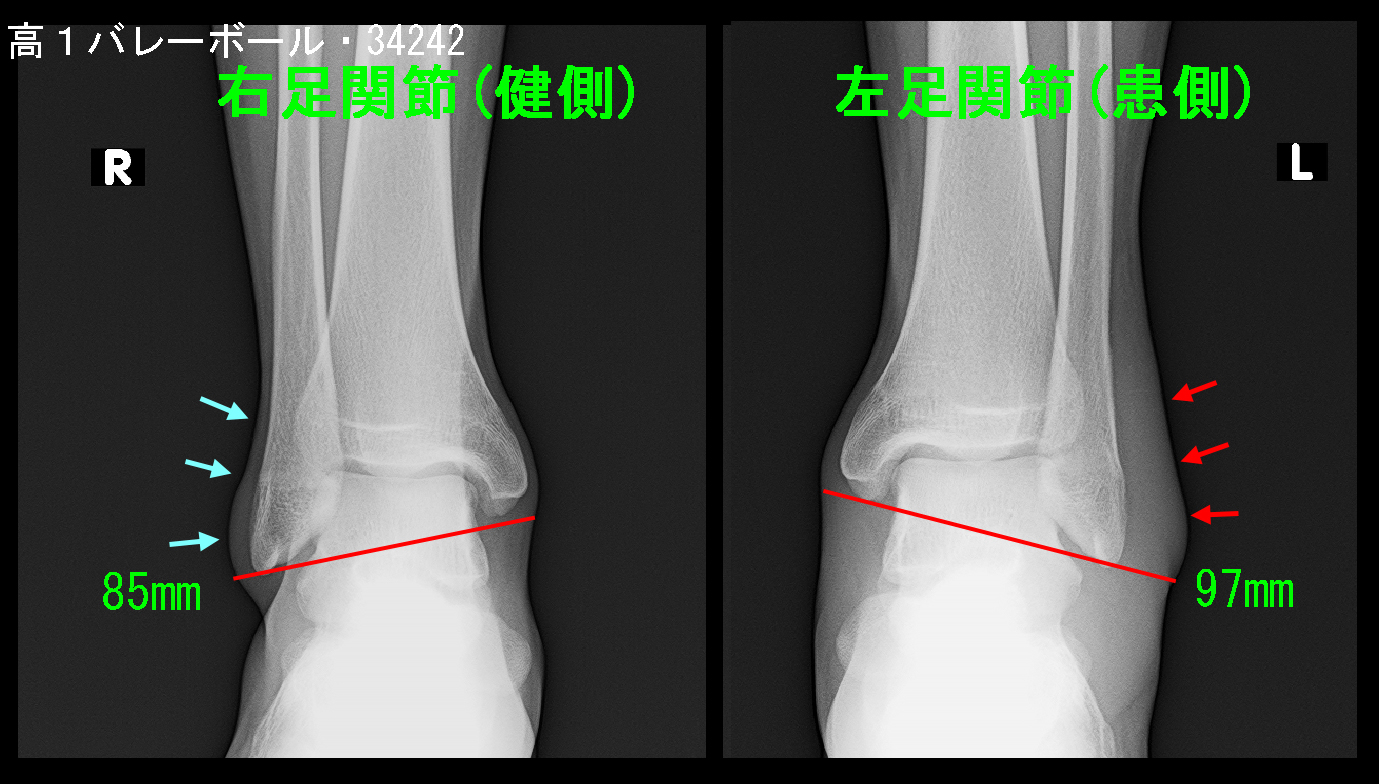

受診時両側の足関節レントゲン像ですが、健側の右足関節では足関節の内果・外果部の皮膚は骨の直ぐ上となりますが、患側の左足関節では外果部の皮膚は骨から分厚くなっています(赤矢印)。外傷による腫脹の結果です。外果部と内果部を結ぶ幅は健側では85mmで、患側は97mmで、周囲径としては(円周率をかけた)3.8㎝の差でズボンのサイズとしても4㎝も違うとかなり腫れていることが推察されます。